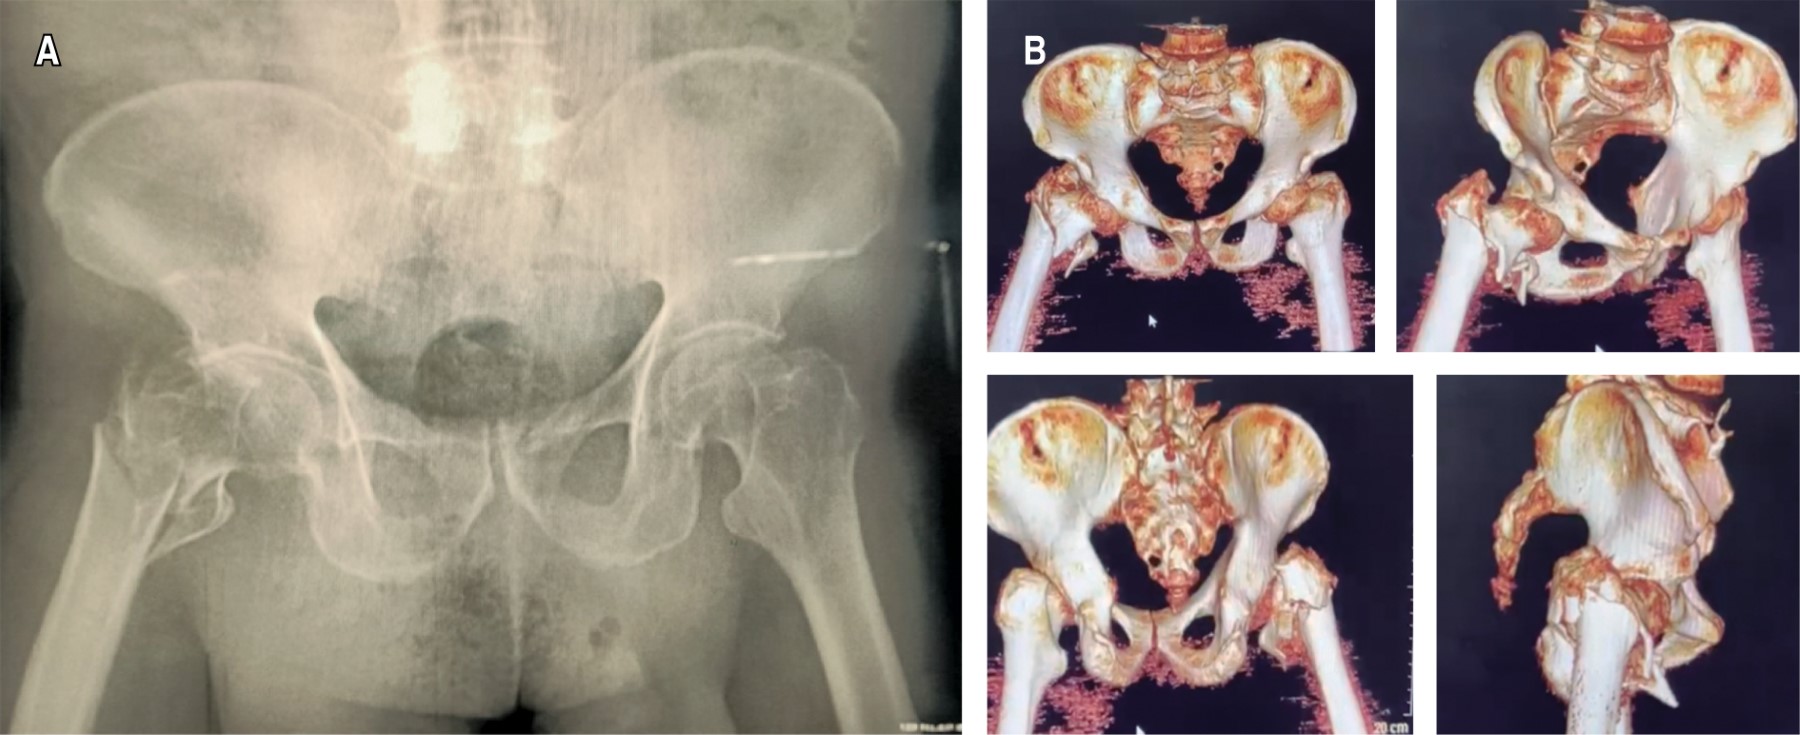

Hombre de 79 años de edad, jubilado. Quien no tiene antecedentes personales de interés para el caso clínico, solamente hernia inguinal indirecta derecha de años de evolución, no cuenta con antecedentes ortopédicos, tabaquismo positivo, niega toxicomanías y alcoholismo. El paciente refiere que, mientras caminaba por superficie irregular en una sierra, sufre caída de su propia altura posterior a "pisar mal", cayendo con un mecanismo de hiperflexión de la cadera derecha realizando un "split", con lo que presenta de forma súbita incapacidad para reincorporarse, coxalgia derecha y posición distinta de miembro pélvico derecho al contralateral, incapaz de movilizar. A su llegada a urgencias, tras exploración física dirigida, extremidad pélvica derecha con importante acortamiento y rotación externa. Estudios de gabinete: se solicita proyección radiográfica (Figura 1A); por la complejidad del trazo, se decide solicitar tomografía axial computada para definir mejor la fractura (Figura 1B).

Figura 1